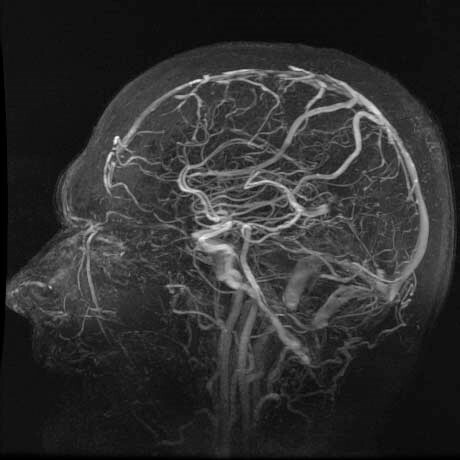

MRA - Magnetic Resonance Angiography

What is an MRA?

Intracranial MRA images collage

Intracranial MRA

MRA stands for magnetic resonance angiography. It is an MRI study of the blood vessels. MRAs are used to assess abnormalities in the blood vessels of patients with a history of stroke, aneurysm, heart disease, and atherosclerotic vascular disease.

Why might my doctor recommend an MRA?

Your doctor might recommend an MRA if you suffer from frequent headaches. Often, MRAs also are used to evaluate problems with blood vessels such as disease and narrowing or enlargement. Additionally, MRA is helpful in detecting disease in arteries supplying blood to the brain and the development of atherosclerosis, a condition that can lead to stroke. MRA is a useful tool to detect aneurysms and evaluate your veins.